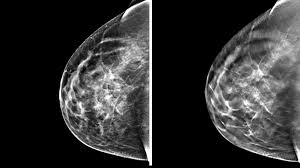

We'll show you breast cancer pictures to help you identify any physical traits of the condition. More importantly, the overlap can obscure small breast cancers. What does breast cancer look like on a mammogram? The outer edges of these cells look fuzzy or spiky (called spiculated). The doctor reading your mammogram will be looking for different types of breast changes, such as small white spots called calcifications, larger abnormal areas called masses, and other suspicious areas that could be signs of cancer.

Most screening mammograms include two views of each breast taken from different angles. Abnormalities such as cancerous tumors usually appear brighter because they are denser. Any area that does not look like normal tissue is a possible cause for concern. However, 3d allows us to 'slice through' the breast, making thin sections, like on a ct scan. A diagnostic mammogram is used to check for breast cancer when there is a sign or symptom of disease. These deposits show up as tiny white spots on a mammogram, and there may be only one or two, or too many to count, says jay baker, md, a breast imaging specialist at the duke cancer center. 1 the gray areas correspond to normal fatty tissue, while the white areas are normal breast tissue with ducts and lobes. A 3d mammogram is used to look for breast cancer in people who have no signs or symptoms. Screening mammograms have been used since the 1980s. Dense breast tissue appears solid. Digital breast tomosynthesis (tomo), also known as 3d mammography, is a revolutionary new screening and diagnostic breast imaging tool to improve the early detection of breast cancer. Moose & doc breast cancer, 21 may 2018. Calcifications are calcium deposits within the breast tissue and they look like small white spots.

Mammogram Images Normal Abnormal And Breast Cancer from cdn-prod.medicalnewstoday.com The doctor reading your mammogram will be looking for different types of breast changes, such as small white spots called calcifications, larger abnormal areas called masses, and other suspicious areas that could be signs of cancer. What does breast cancer look like? That makes it easy to detect abnormalities, which generally show up as white. Normal breast tissue can look 100,000 different ways on a mammogram. This decreases the overlap and makes it easier to see cancers. additionally, the combination of 2d and 3d mammogram imaging has been shown to reduce false positives that require a patient to return to the clinic for additional screening. Bright spots on a mammogram that look like potential tumors could turn out to be overlapping tissues or a blood vessel folding over on itself, friedewald said. 1 the gray areas correspond to normal fatty tissue, while the white areas are normal breast tissue with ducts and lobes. This overlapping tissue can cause the resulting image to look like cancer.